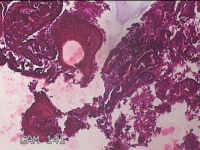

宫腔内容物

性别

女

年龄

46岁

临床诊断

子宫异常出血 子宫内膜息肉?高泌乳素血症待查 慢性宫颈炎

一般病史

阴道流血不规则22天。

标本名称

大体所见

灰白暗红色不规则碎组织3.3x2.8x0.7cm一堆。